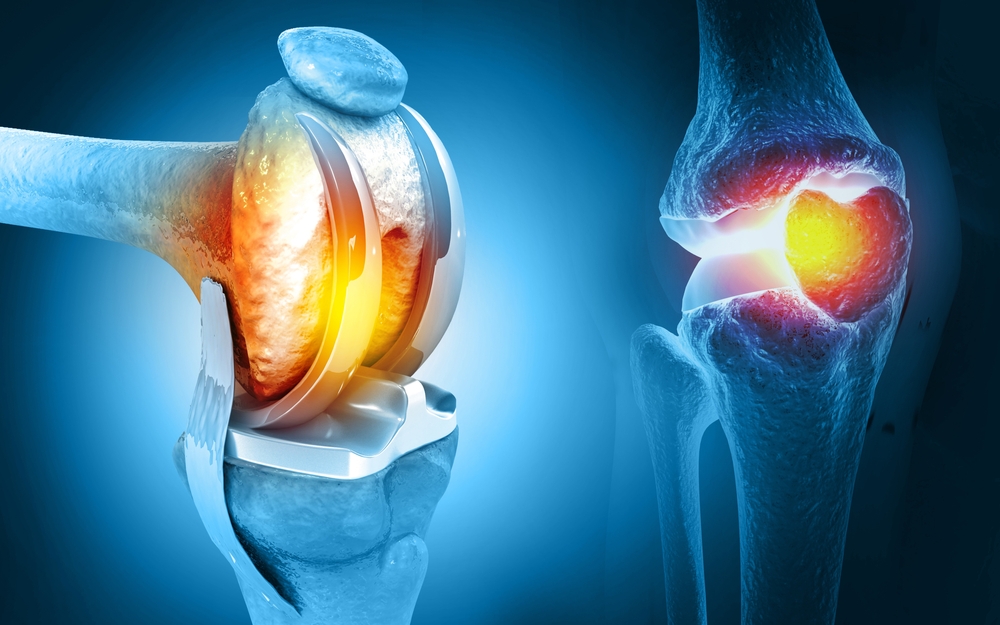

For severe joint damage from conditions like osteoarthritis or injury, Dr. Harish Talreja performs joint replacement surgeries, such as knee or hip replacements.

Knee Replacement

Hip Replacement

Knee Replacement

Hip Replacement

घुटने का दर्द! ये दो शब्द सुनते ही ज्यादातर लोगों के चेहरे पर परेशानी आ जाती है. चलने-फिरने में दिक्कत, सीढ़ियां चढ़ने में तकलीफ, ये सब घुटने के दर्द के आम लक्षण हैं.